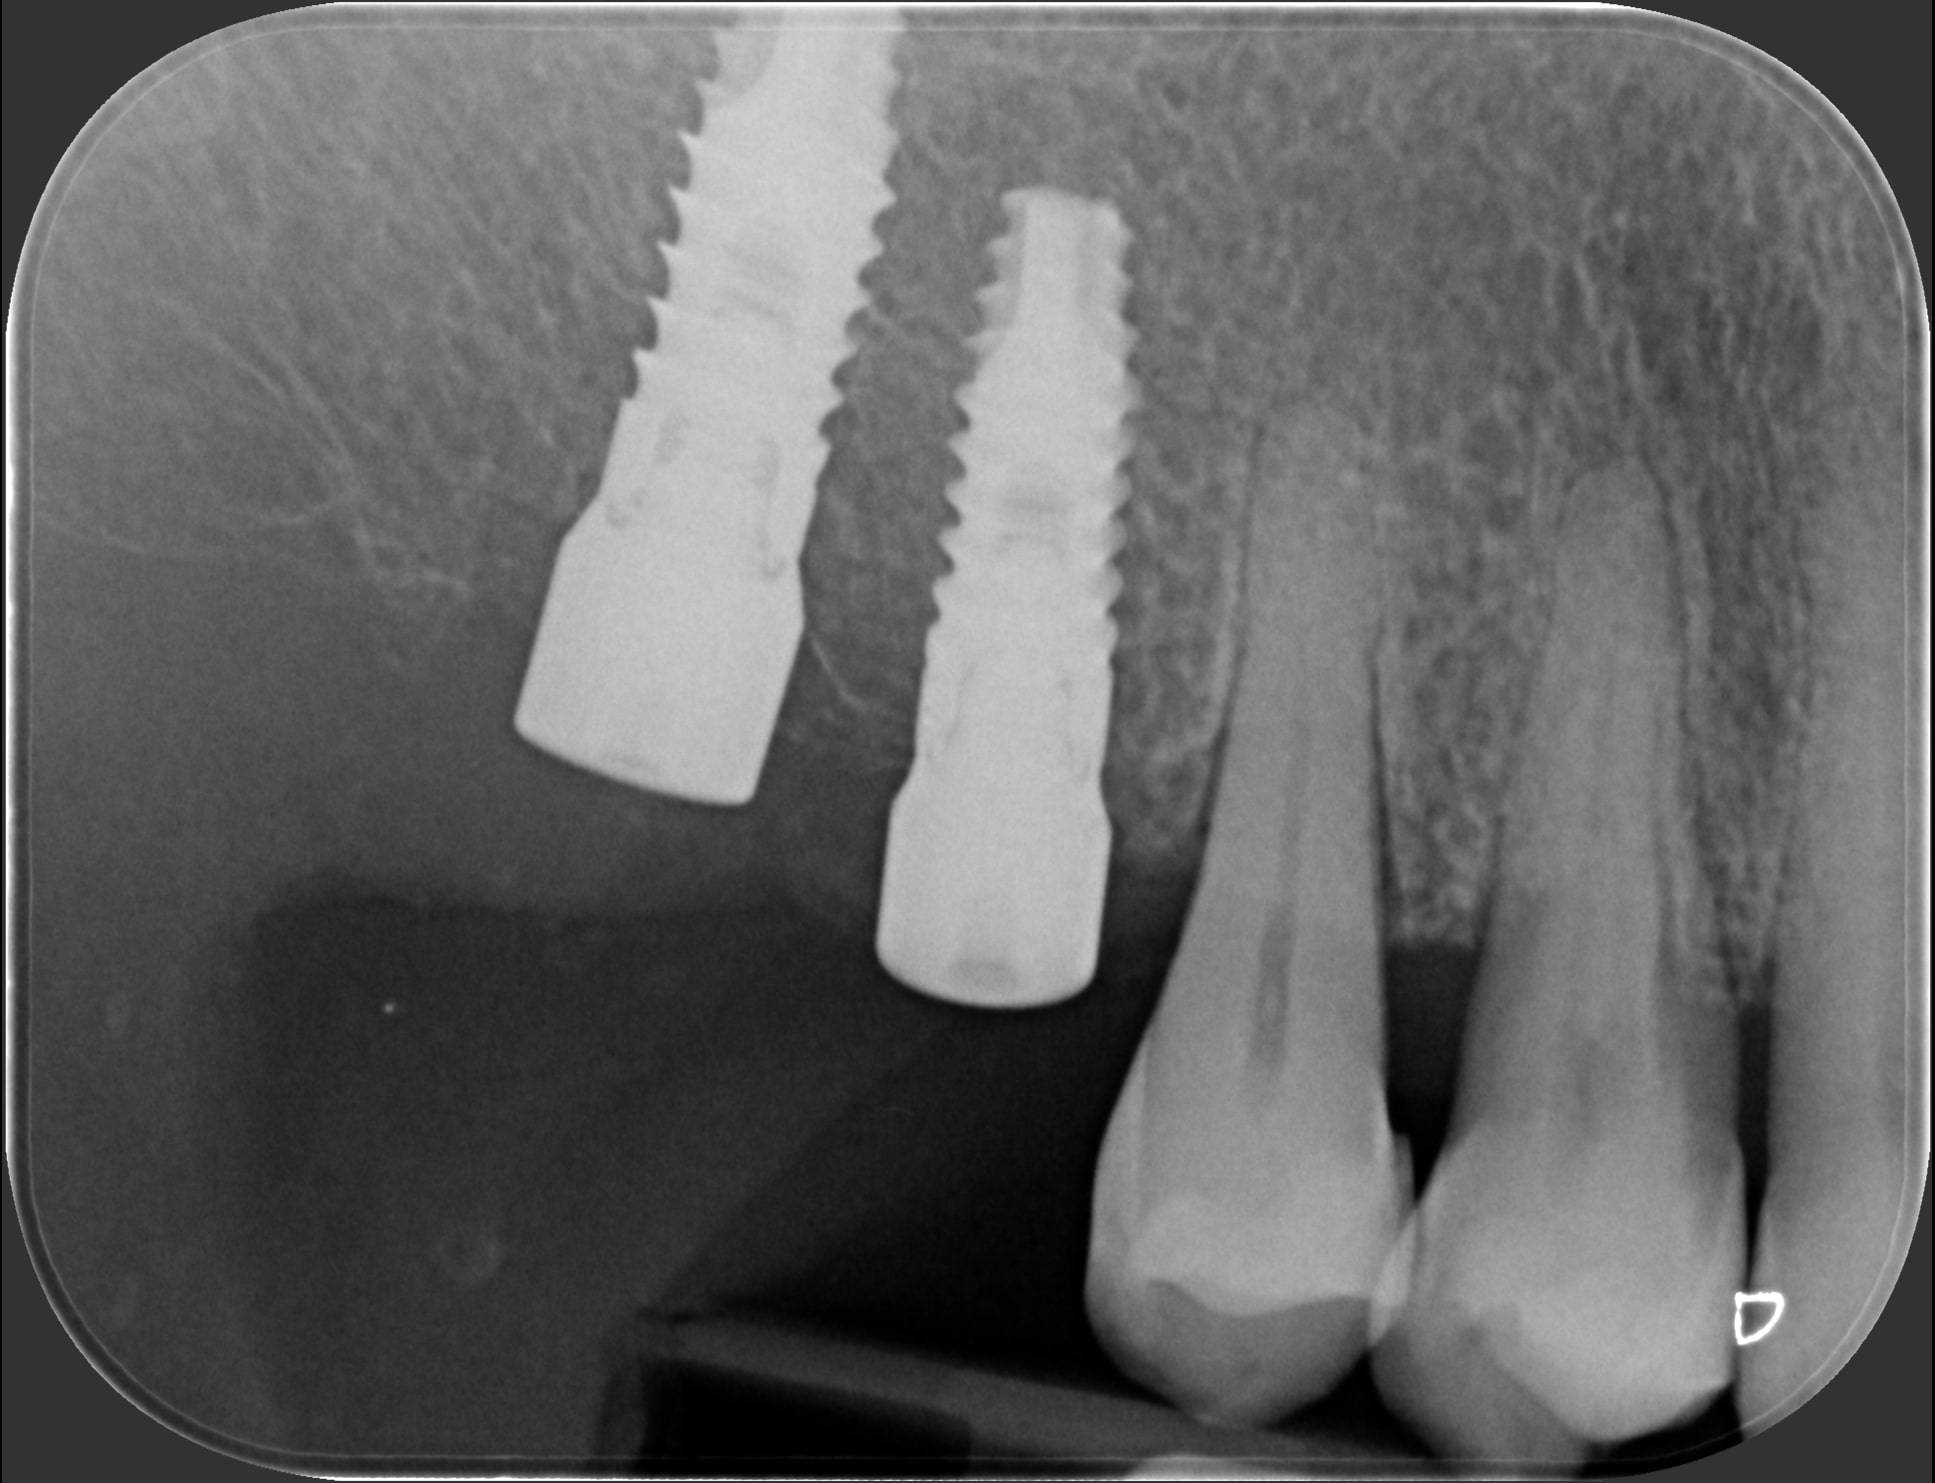

Un laboratorio specializzato ha creato una dima in resina nella quale ci sono degli anelli metallici che mi hanno guidato a posizionare gli impianti esattamente secondo quanto programmato al computer. Nella prima foto puoi vedere com’è fatta la dima: si vedono chiaramente 6 anelli esagonali (2 a destra della paziente e 4 a sinistra), dentro cui ho inserito le frese per creare la strada agli impianti, che ho avvitato poco dopo. Una volta posizionata la dima sui denti, è facilissimo e veloce posizionare gli impianti seguendo le guide metalliche. Infatti nelle foto successive si vedono le radiografie degli impianti messi dentro l’osso in modo perfettamente paralleli fra loro, 2 a destra e 4 a sinistra, proprio come da progettazione virtuale. La profondità, l’angolazione e la distanza tra i vari impianti sono state calcolate attraverso il computer prima ancora di eseguire l’intervento, con una precisione che è difficile raggiungere con un intervento a mano libera. Le radiografie parlano da sole. Dott. Fabio Ballestrasse, Besana Brianza (MB).